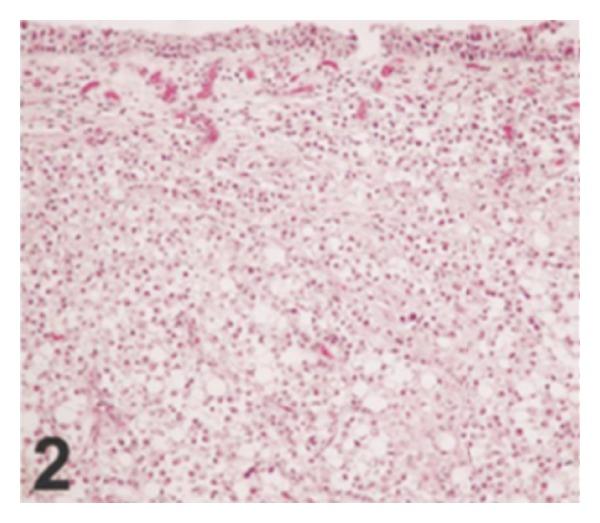

Background. Nested variant of urothelial carcinoma was added to the WHO's classification in 2004. Aims. To review the literature on nested variant of urothelial carcinoma. Results. About 200 cases of the tumour have been reported so far and it has the ensuing morphological features: large numbers of small confluent irregular nests of bland-appearing, closely packed, haphazardly arranged, and poorly defined urothelial cells infiltrating the lamina propria and the muscularis propria. The tumour has a bland histomorphologic appearance, has an aggressive biological behaviour, and has at times been misdiagnosed as a benign lesion which had led to a significant delay in the establishment of the correct diagnosis and contributing to the advanced stage of the disease. Immunohistochemically, the tumour shares some characteristic features with high-risk conventional urothelial carcinomas such as high proliferation index and loss of p27 expression. However, p53, bcl-2, or EGF-r immunoreactivity is not frequently seen. The tumour must be differentiated from a number of proliferative lesions of the urothelium. Conclusions. Correct and early diagnosis of this tumour is essential to provide early curative treatment to avoid diagnosis at an advanced stage. A multicentre trial is required to identify treatment options that would improve the outcome of this tumour.

背景。尿路上皮癌巢状变异型于2004年被纳入世界卫生组织分类。目的。回顾关于尿路上皮癌巢状变异型的文献。结果。迄今为止已报道了约200例该肿瘤病例,其具有以下形态学特征:大量小的融合性不规则巢状结构,由外观温和、紧密排列、杂乱无章且边界不清的尿路上皮细胞组成,浸润固有层和肌层。该肿瘤具有温和的组织形态学外观,具有侵袭性生物学行为,有时被误诊为良性病变,这导致正确诊断的建立出现显著延迟,并促使疾病进展至晚期。免疫组织化学方面,该肿瘤与高危传统尿路上皮癌具有一些共同特征,如高增殖指数和p27表达缺失。然而,p53、bcl-2或表皮生长因子受体免疫反应性并不常见。该肿瘤必须与多种尿路上皮增生性病变相鉴别。结论。对该肿瘤进行正确和早期诊断对于提供早期治愈性治疗以避免晚期诊断至关重要。需要进行多中心试验以确定可改善该肿瘤治疗结果的治疗方案。